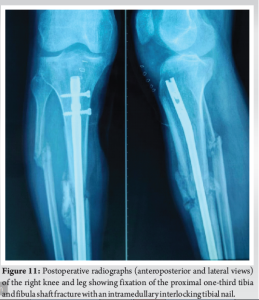

On the right side, the fractured 8th rib was reduced and stabilized with a 2 mm reconstruction plate. The wound was closed with a negative-pressure drain to prevent hematoma formation, which was removed after 48 h.Post-op X-ray (Fig. 7) shows well-aligned and reduced sternum with no evidence of pneumothorax or hemothorax.The open wound on the medial aspect of the proximal tibia (Fig. 8) was initially managed with urgent debridement, for the proximal tibia 1/3rd shaft fracture (Fig.-9) application of an external fixator (Fig. 10), and initiation of negative pressure wound therapy. After ensuring the wound was healthy, a flap coverage procedure was done by the plastic surgery team. Following flap maturation, the external fixator was removed, and the patient underwent closed reduction and internal fixation using tibial interlocking (intramedullary interlocking) nailing (Fig. 11).